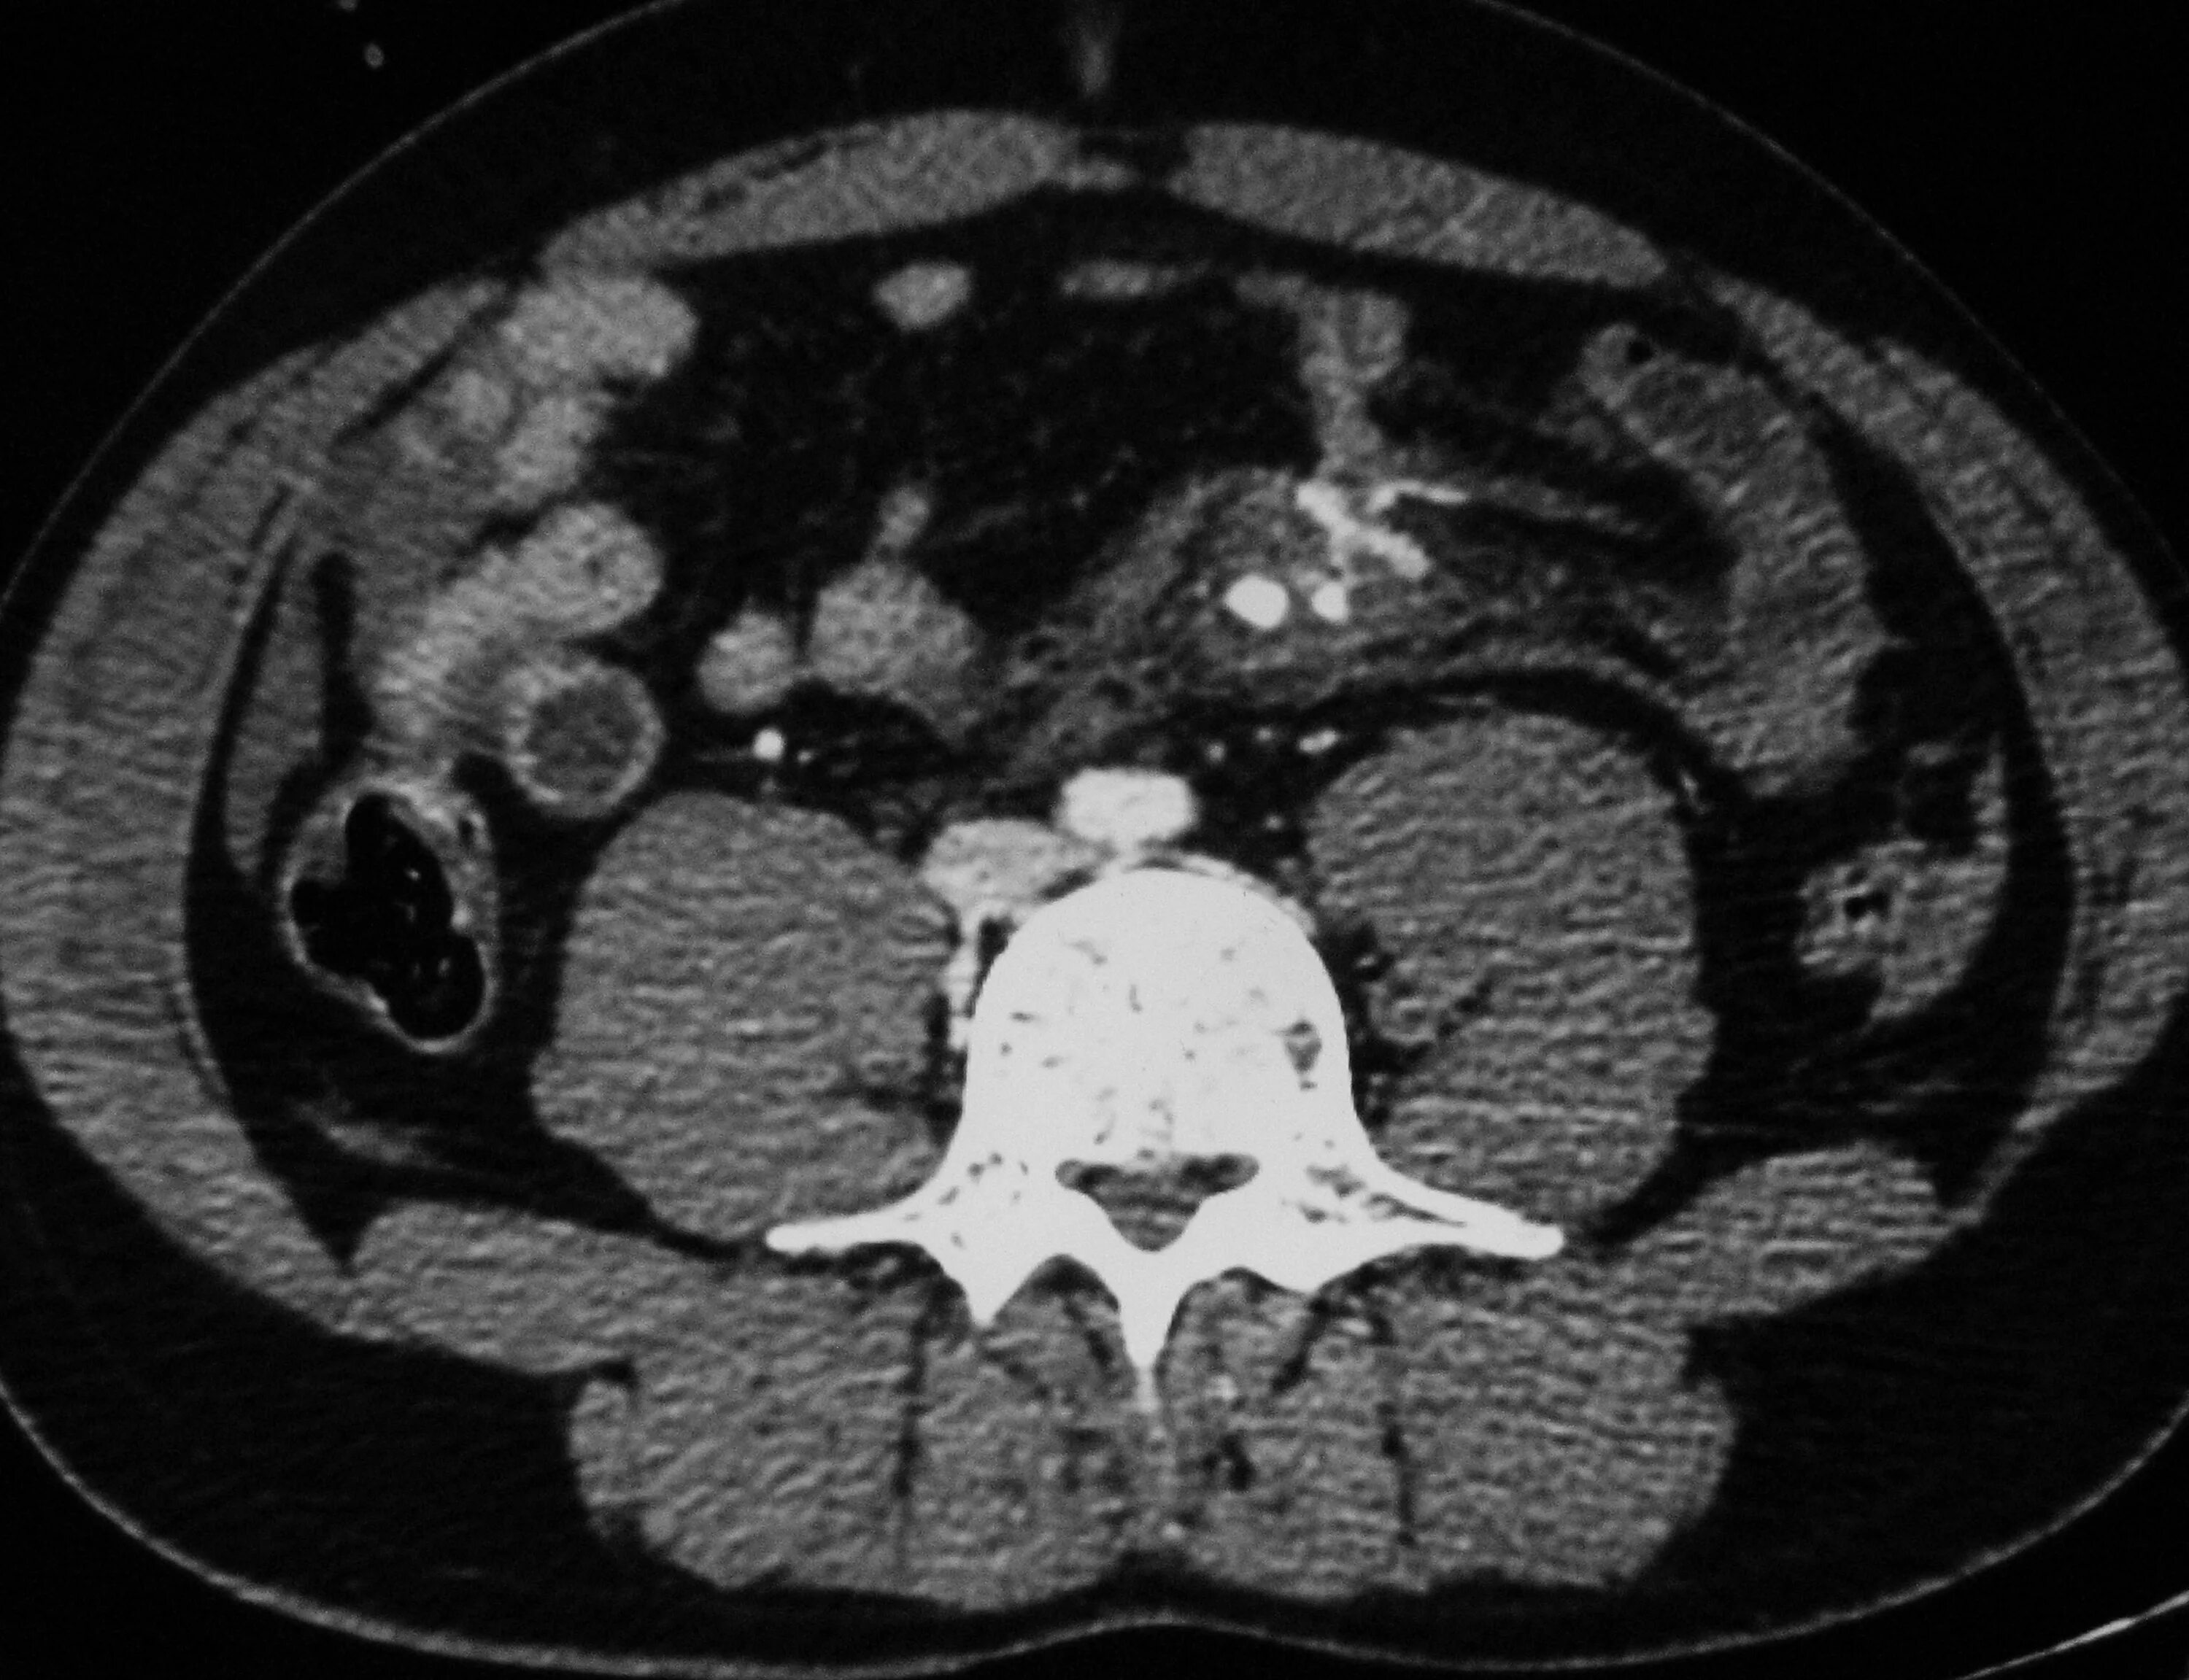

Обследование кт кишечника